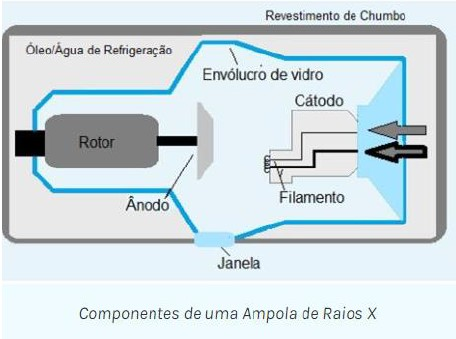

O TUBO DE RAIOS X é um componente do aparelho de raios X de conhecimento do técnico de radiologia. Ele está contido em uma caixa de proteção e, portanto, é inacessível. A figura a seguir apresenta um diagrama esquemático de um tubo de raios X diagnóstico com um anodo giratório. Seus componentes são considerados separadamente, mas deve estar claro que existem duas partes principais: o catodo e o anodo. Cada uma delas é um eletrodo, e qualquer tubo com dois eletrodos é um diodo. Vários são os componentes que fazem parte dessa estrutura pela emissão dos raios. Com isso, o técnico deve ter o saber de cada componente. Considerando o que foi explanado analise as afirmações a seguir.

https://ampoladigital.wordpress.com/2016/10/04/producao-de-radiacao-x/, acesso dia 13/11/2023.

I. O invólucro protetor de alguns tubos de raios X contém óleo, que serve tanto como isolante contra choques elétricos quanto como manta térmica para dissipação do calor.

II. A ampola mantém o vácuo no interior do tubo. Esse vácuo permite mais eficiência na produção dos raios X e uma vida mais longa do tubo.

III. Um filamento de tubo de raios X emite elétrons quando é aquecido. Quando a corrente através do filamento é suficientemente elevada, os elétrons das camadas mais externas dos átomos do filamento são “agitados” e ejetados do filamento. Esse fenômeno é conhecido como emissão de termiônica.

IV. A maioria dos tubos de raios X de anodo giratório tem dois filamentos montados lado a lado no suporte do catodo, gerando tamanhos de pontos focais grandes e pequenos.

V. Tubos de raios X especiais para mamografia têm alvos de molibdênio ou ródio principalmente devidos a seu baixo número atômico e baixa energia dos raios X característicos da camada K.